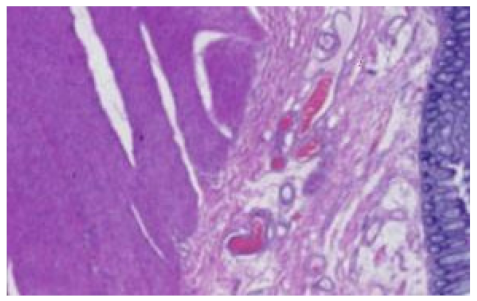

In the data collection phase, we obtained H&E-stained slides used in an external quality assessment (EQA) round organized by Labquality (Helsinki, Finland), a company providing external quality assessment schemes for clinical laboratories. The slides had a tissue microarray section consisting of three 6 mm punch biopsies. The punches were taken from normal human kidney, skin, and colon samples. The samples were anonymous formalin-fixed and paraffin-embedded routine histologic samples from a reference pathology laboratory. The EQA round was organized such that unstained 3 µm sections were sent to laboratories participating in the EQA scheme. The laboratories were asked to stain the slides by the H&E method they use in their daily practice. Altogether 66 laboratories from 11 countries returned the slides for the assessment. After that, the slides were digitalized with a NanoZoomer-XR (Hamamatsu Photonics) slide scanner with a 20× objective (scanning resolution 0.46 μm/pix); Figure 1 shows a random example of a stained slide.

Figure 1.

Randomly chosen WSI, label 1 for kidney, 2 for skin, and 3 for colon tissue.